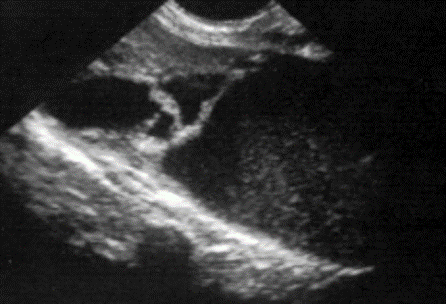

What is going on here?

Abscess

Hypoenchoic

Infalmmatory disease

From the acute prostatis